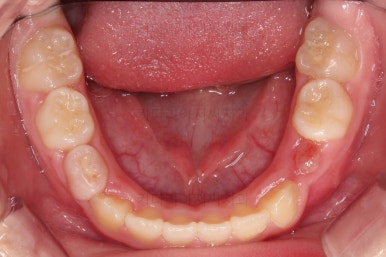

초진 시 입안의 모습입니다.

아래쪽 치열이 전반적으로 윗니보다 앞쪽에 위치한 전형적인 앵글씨 3급 부정교합인데요.

어금니에서부터 앞니까지 아랫니가 윗니보다 앞쪽에 위치하네요.

특히 앞니는 아랫니가 윗니보다 나와있는 "반대교합" 상태였고요.

또한 위아래로 겹침이 없고 떠있는 "개방교합" 상태였어요.

즉, 앵글씨 3급 부정교합 - 반대교합 - 개방교합 등 굉장히 복합적인 교합의 문제를 가진 환자였습니다.